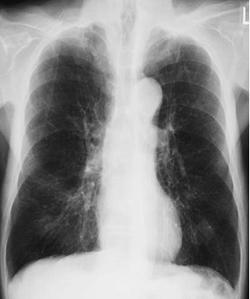

P波の増高は、肺高血圧症や肺気腫、心房中隔欠損症など、右心房に負荷がかかる疾患でみられる。心筋梗塞とは関係がない。